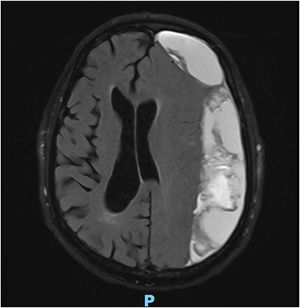

Con la sospecha diagnóstica de una demencia de rápida evolución con alteración de la marcha asociada a signos indirectos ecográficos de hipertensión endocraneal, se programa RMN craneal urgente (fig. 2).

Con el resultado de hematoma subdural extenso e hipertensión endocraneal se deriva a Neurocirugía, donde se realiza craniectomía urgente con evacuación del hematoma. A las 48h había una mejoría de la situación cognitiva con una recuperación de la memoria episódica verbal (7 puntos sobre 8 en el test Memory Impairment Screen) y en la orientación temporal (4/5 en el subtest del MMSE). La marcha había mejorado sobre todo el componente de la estabilidad, logrando no precisar ayuda en trayectos cortos (10m).